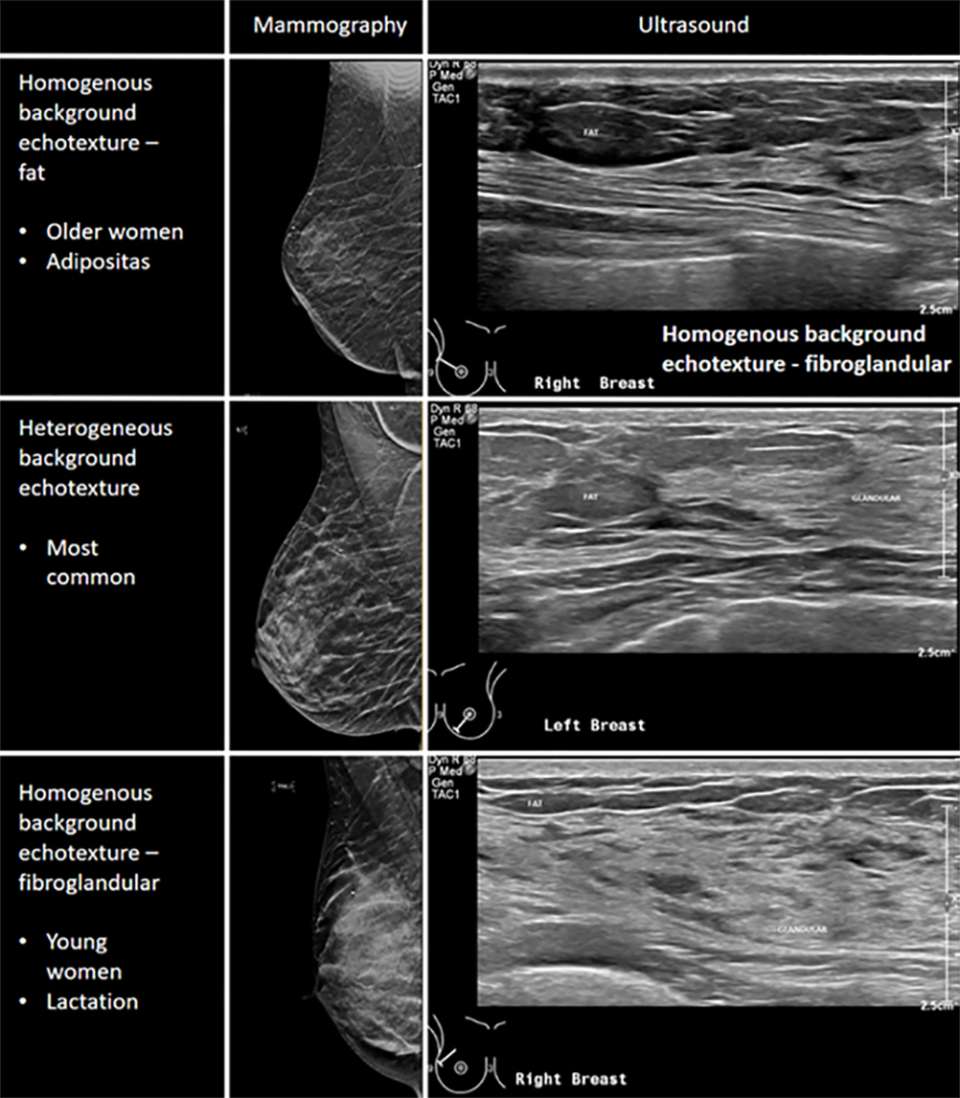

The breast is comprised of a mixture of fatty and fibroglandular tissue. This glandular tissue may be heterogeneously spread throughout the breast, usually more prominent within the upper outer quadrant and centrally in the breast. Glandular tissue can be affected by hormonal fluctuations, for example during the menstrual cycle, pregnancy, or lactation. Additional factors such as medications and age will affect the density of the breast tissue. Based on the Breast Imaging Reporting & Data System (BI-RADS), the lexicon to describe breast tissue composition include homogenous background echotexture – fat, homogenous background echotexture – fibroglandular, heterogeneous background echotexture.